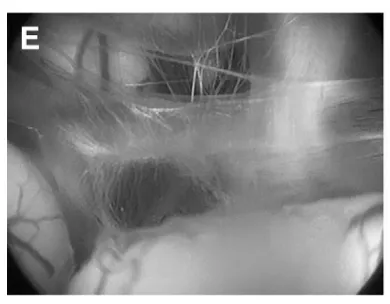

(E)经造瘘口窥见基底动脉。